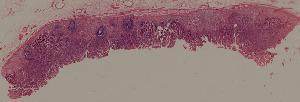

59. Chronic atrophic gastritis